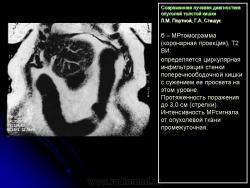

Протокол исследования включал применение импульсных последовательностей (ИП): SE в режиме Т1 с компенсацией дыхания, FSE, STIR (Т2 с синхронизацией дыхания). Основными МРсимптомами опухолевого поражения стенки кишки являются: неравномерное ее утолщение на ограниченном протяжении с соответствующим сужением просвета кишки, наличие внутрипросветного образования с неровными очертаниями и из менением МРсигнала (рис. 14). Толщина пораженной стенки кишки составляла от 7 до 40 мм. Очертания внутренних контуров стенки на уровне поражения были не ровные, бугристые. Интенсивность МРсигнала от из мененной стенки как на Т1, так и на Т2 ВИ была промежуточной (рис. 15), однородность сигнала зависела от преобладания процессов, развивающихся в опухолевой ткани: при имеющихся зонах распада на Т2 ВИ выявлялись очаги повышенной интенсивности МРсигнала. При использовании программы STIR интенсивность сигнала от опухолевой ткани была высокой. Распространение опухолевой инфильтрации за пределы стенки кишки характеризовалось нечеткостью наружных границ опухоли, сетчатым рисунком клетчатки с гетерогенным изменением Мрсигнала, более выраженным на Т1 ВИ (рис. 16б). При прорастании опухоли в смежные органы и структуры не визуализировались границы между измененной стенкой кишки и органом, на который распространялась опухолевая инфильтрация (рис. 17).